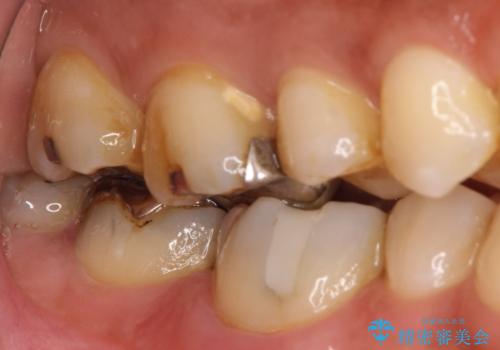

- 左上の奥歯がズキズキ痛い、冷たいものも長引く痛みがあると来院されました。

根管治療を行った後にオールセラミッククラウンにて修復しております。